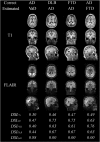

Different neurodegenerative diseases can cause memory disorders and other cognitive impairments. The early detection and the stratification of patients according to the underlying disease are essential for an efficient approach to this healthcare challenge. This emphasizes the importance of differential diagnostics. Most studies compare patients and controls, or Alzheimer's disease with one other type of dementia. Such a bilateral comparison does not resemble clinical practice, where a clinician is faced with a number of different possible types of dementia. Here we studied which features in structural magnetic resonance imaging (MRI) scans could best distinguish four types of dementia, Alzheimer's disease, frontotemporal dementia, vascular dementia, and dementia with Lewy bodies, and control subjects. We extracted an extensive set of features quantifying volumetric and morphometric characteristics from T1 images, and vascular characteristics from FLAIR images. Classification was performed using a multi-class classifier based on Disease State Index methodology. The classifier provided continuous probability indices for each disease to support clinical decision making. A dataset of 504 individuals was used for evaluation. The cross-validated classification accuracy was 70.6% and balanced accuracy was 69.1% for the five disease groups using only automatically determined MRI features. Vascular dementia patients could be detected with high sensitivity (96%) using features from FLAIR images. Controls (sensitivity 82%) and Alzheimer's disease patients (sensitivity 74%) could be accurately classified using T1-based features, whereas the most difficult group was the dementia with Lewy bodies (sensitivity 32%). These results were notable better than the classification accuracies obtained with visual MRI ratings (accuracy 44.6%, balanced accuracy 51.6%). Different quantification methods provided complementary information, and consequently, the best results were obtained by utilizing several quantification methods. The results prove that automatic quantification methods and computerized decision support methods are feasible for clinical practice and provide comprehensive information that may help clinicians in the diagnosis making.